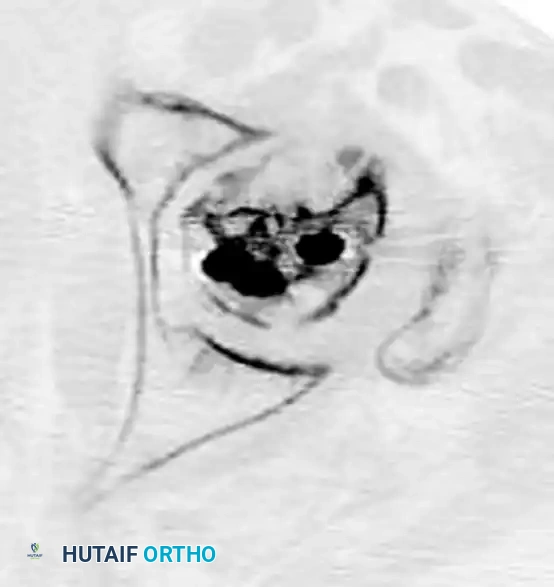

While osteonecrosis (avascular necrosis) is classically associated with intracapsular femoral neck fractures, proximal femoral trauma and its subsequent surgical management can occasionally compromise the vascular supply to the femoral head, particularly in combined fracture patterns or following aggressive surgical dissection.

FIGURE 55-19 Osteonecrosis after treatment of proximal femoral fracture. Anteroposterior radiograph (A), axial CT scan (B), and coronal CT scan (C) demonstrating advanced collapse and hardware penetration.